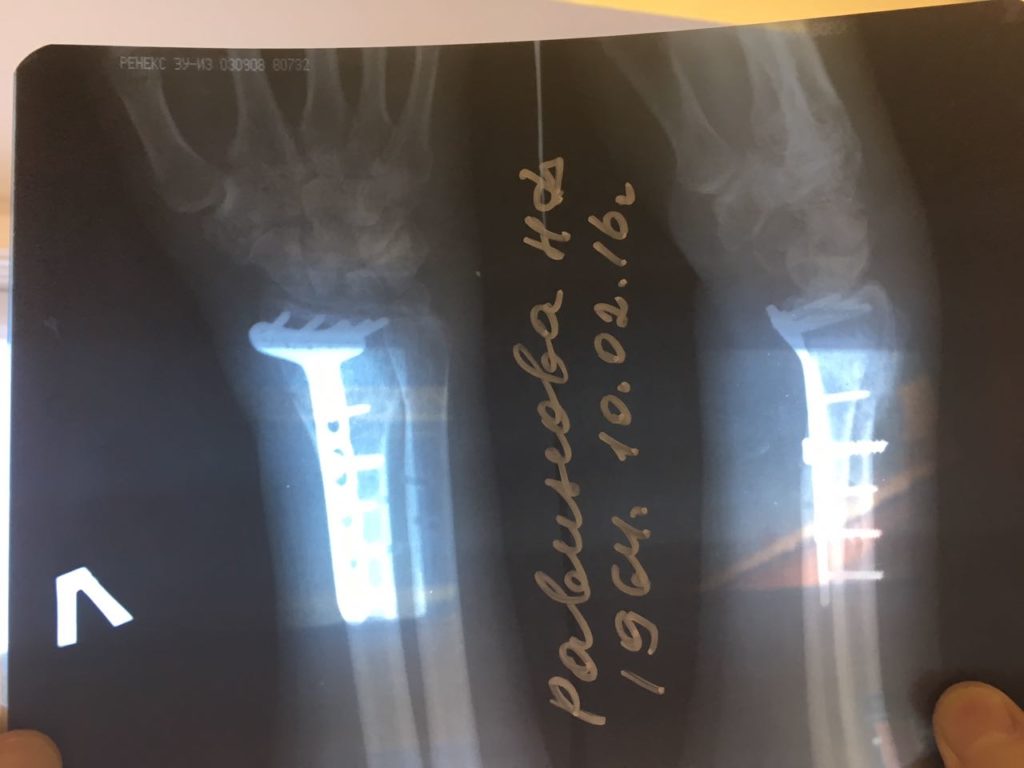

Операция - открытая репозиция, остеосинтез лучевой кости пластиной с костной ксенопластикой материалом "Остеоматрикс". На контрольных снимках в три месяца имеется консолидация перелома, миграции фиксатора нет, имеется остеоинтеграция ксенопластического материала.

Отдаленные результаты через 3 (три) месяца: